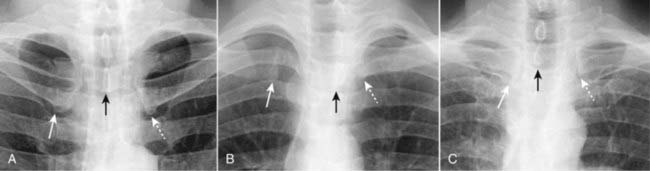

Rotation

image Significant rotation (the patient turns the body to one side or the other) may alter the expected contours of the heart and great vessels, the hila, and hemidiaphragms.

image The easiest way to assess whether the patient is rotated toward the left or right is by studying the position of the medial ends of each clavicle relative to the spinous process of the thoracic vertebral body between the clavicles (Fig. 2-14).

The medial ends of the clavicles are anterior structures.

The spinous process is a posterior structure.

If the spinous process appears to lie equidistant from the medial ends of each clavicle on the frontal chest radiograph, there is no rotation (Fig. 2-15A).

If the spinous process appears closer to the medial end of the left clavicle, the patient is rotated toward his own right side (Fig. 2-15B).

If the spinous process appears closer to the medial end of the right clavicle, the patient is rotated toward his own left side (Fig. 2-15C).

These relationships hold true regardless of whether the patient was facing the x-ray tube or the cassette at the time of exposure.

image

Figure 2-14 How to determine if the patient is rotated.

In A, the patient is not rotated and the medial ends of the right (orange dot) and left (black dot) clavicles are projected on the radiograph (black line) equidistant from the spinous process (black triangle). In B, the patient is rotated toward his own right. Notice how the medial end of the left clavicle (black dot) is projected closer to the spinous process than is the medial end of the right clavicle (orange dot). In C, the patient is rotated toward his own left. The medial end of the right clavicle (orange dot) is projected closer to the spinous process than is the medial end of the left clavicle (black dot). The camera icon depicts this as an AP projection, but the same relationships would be true for a PA projection as well. Figure 2-15 shows how this applies to radiographs.

Figure 2-15 How to evaluate for rotation.

A, Close-up view of the heads of the clavicles demonstrates that each (white arrows) is about equidistant from the spinous process of the vertebral body between them (black arrow). This indicates the patient is not rotated. B, Close-up view of the heads of the clavicles in a patient rotated toward his own right (remember that you are viewing the study as if the patient were facing you). The spinous process (black arrow) is much closer to the left clavicular head (dotted white arrow) than it is to the right clavicular head (solid white arrow). C, Close-up view of the heads of the clavicles in a patient rotated toward his own left. The spinous process (black arrow) is much closer to the right clavicular head (solid white arrow) than it is to the left (dotted white arrow).